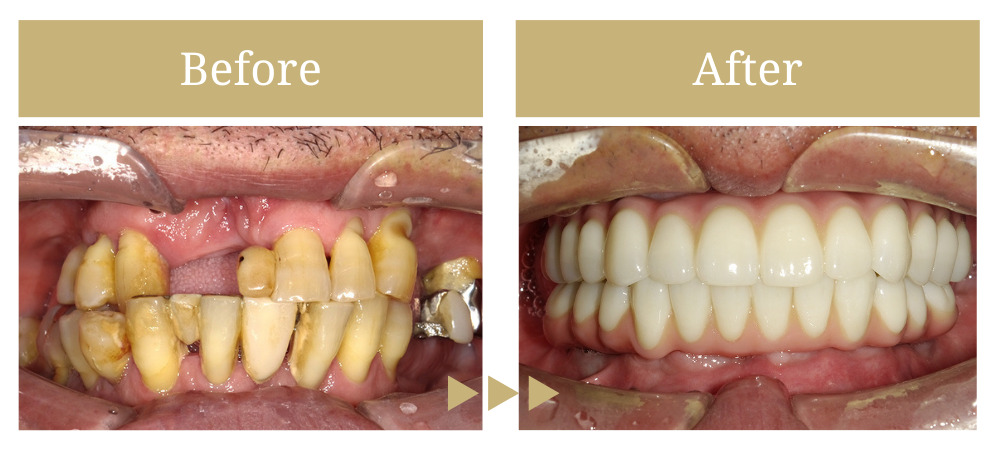

上下顎のオールオン4治療

歯牙動揺による咀嚼障害 (欠損や動揺歯が多く噛めない、入れ歯で痛みが出る)

前歯を含めた複数の部位で歯牙の自然脱落があり、どうにかしたいとご来院されました。

全体的に残存歯は状態が悪く、上顎には歯根露出や動揺が強く見られるため、全顎的な治療が必要と判断しました。

患者様自身は、口内環境に強く不満を持っており、短期間の治療と早期に見た目を改善したいとの希望に沿って、上下オールオン4を行い、審美面の改善と治療の短縮を図りました。

治療後、咀嚼の問題もなくなり、嚙み合わせも安定しました。

「何でも噛むことができるようになっただけでなく、口を隠さずに話すことができるようになった」と非常にお喜び頂けました。